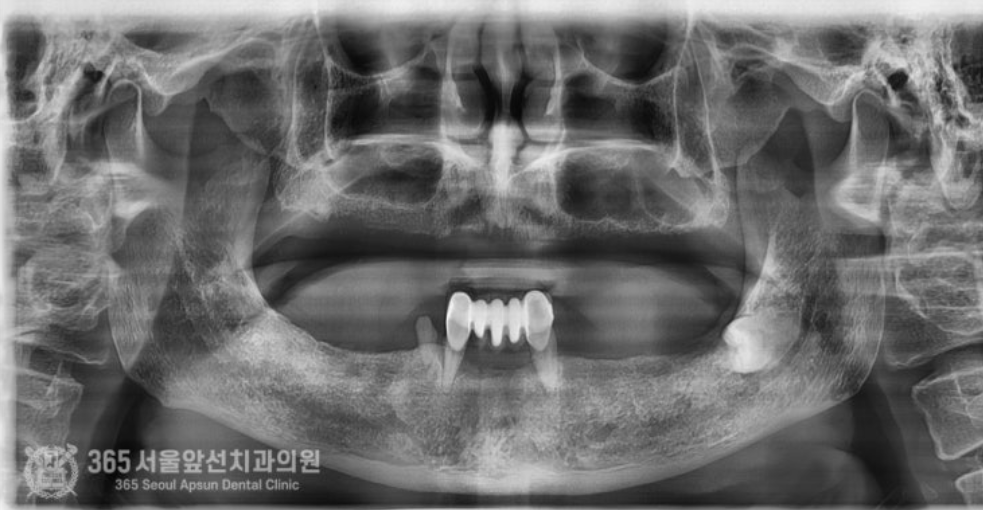

촬영일시 : 2024.05.01 처음 내원 당시 엑스레이 사진입니다. 보시다시피 거의 치아가 남아있지 않고 그나마 남아있는 치아들도 상태가 매우 좋지 않습니다. 아래턱에 치아가 몇개 남아있으나 흔들리고 썩어있는 상태여서 어쩔 수 없이 발치를 하기로 결정하였습니다 ㅠㅠ 이렇게 치아가 있긴 있으나 상태가 좋지 않은 경우에는 오히려 안좋은 치아를 남겨놓고 치료계획을 세울 경우 추후 문제가 되어 전체적인 치료과정에서 문제가 되는 경우가 많기에 발치를 해야할 치아는 늦지 않게 발치를 하고 보철치료나 임플란트 치료로 대체해주는 것이 중요하겠습니다. 환자분께서는 비용 상의 문제로 인해 전체 임플란트를 너무 부담이 되신다고 하셔서 임플란트는 최소한의 갯수로 식립하고 식립된 임플란트를 이용하여 틀니를 튼튼하게 사용할 수 있도록 임플란트 틀니 치료를 하기로 결정하셨습니다.